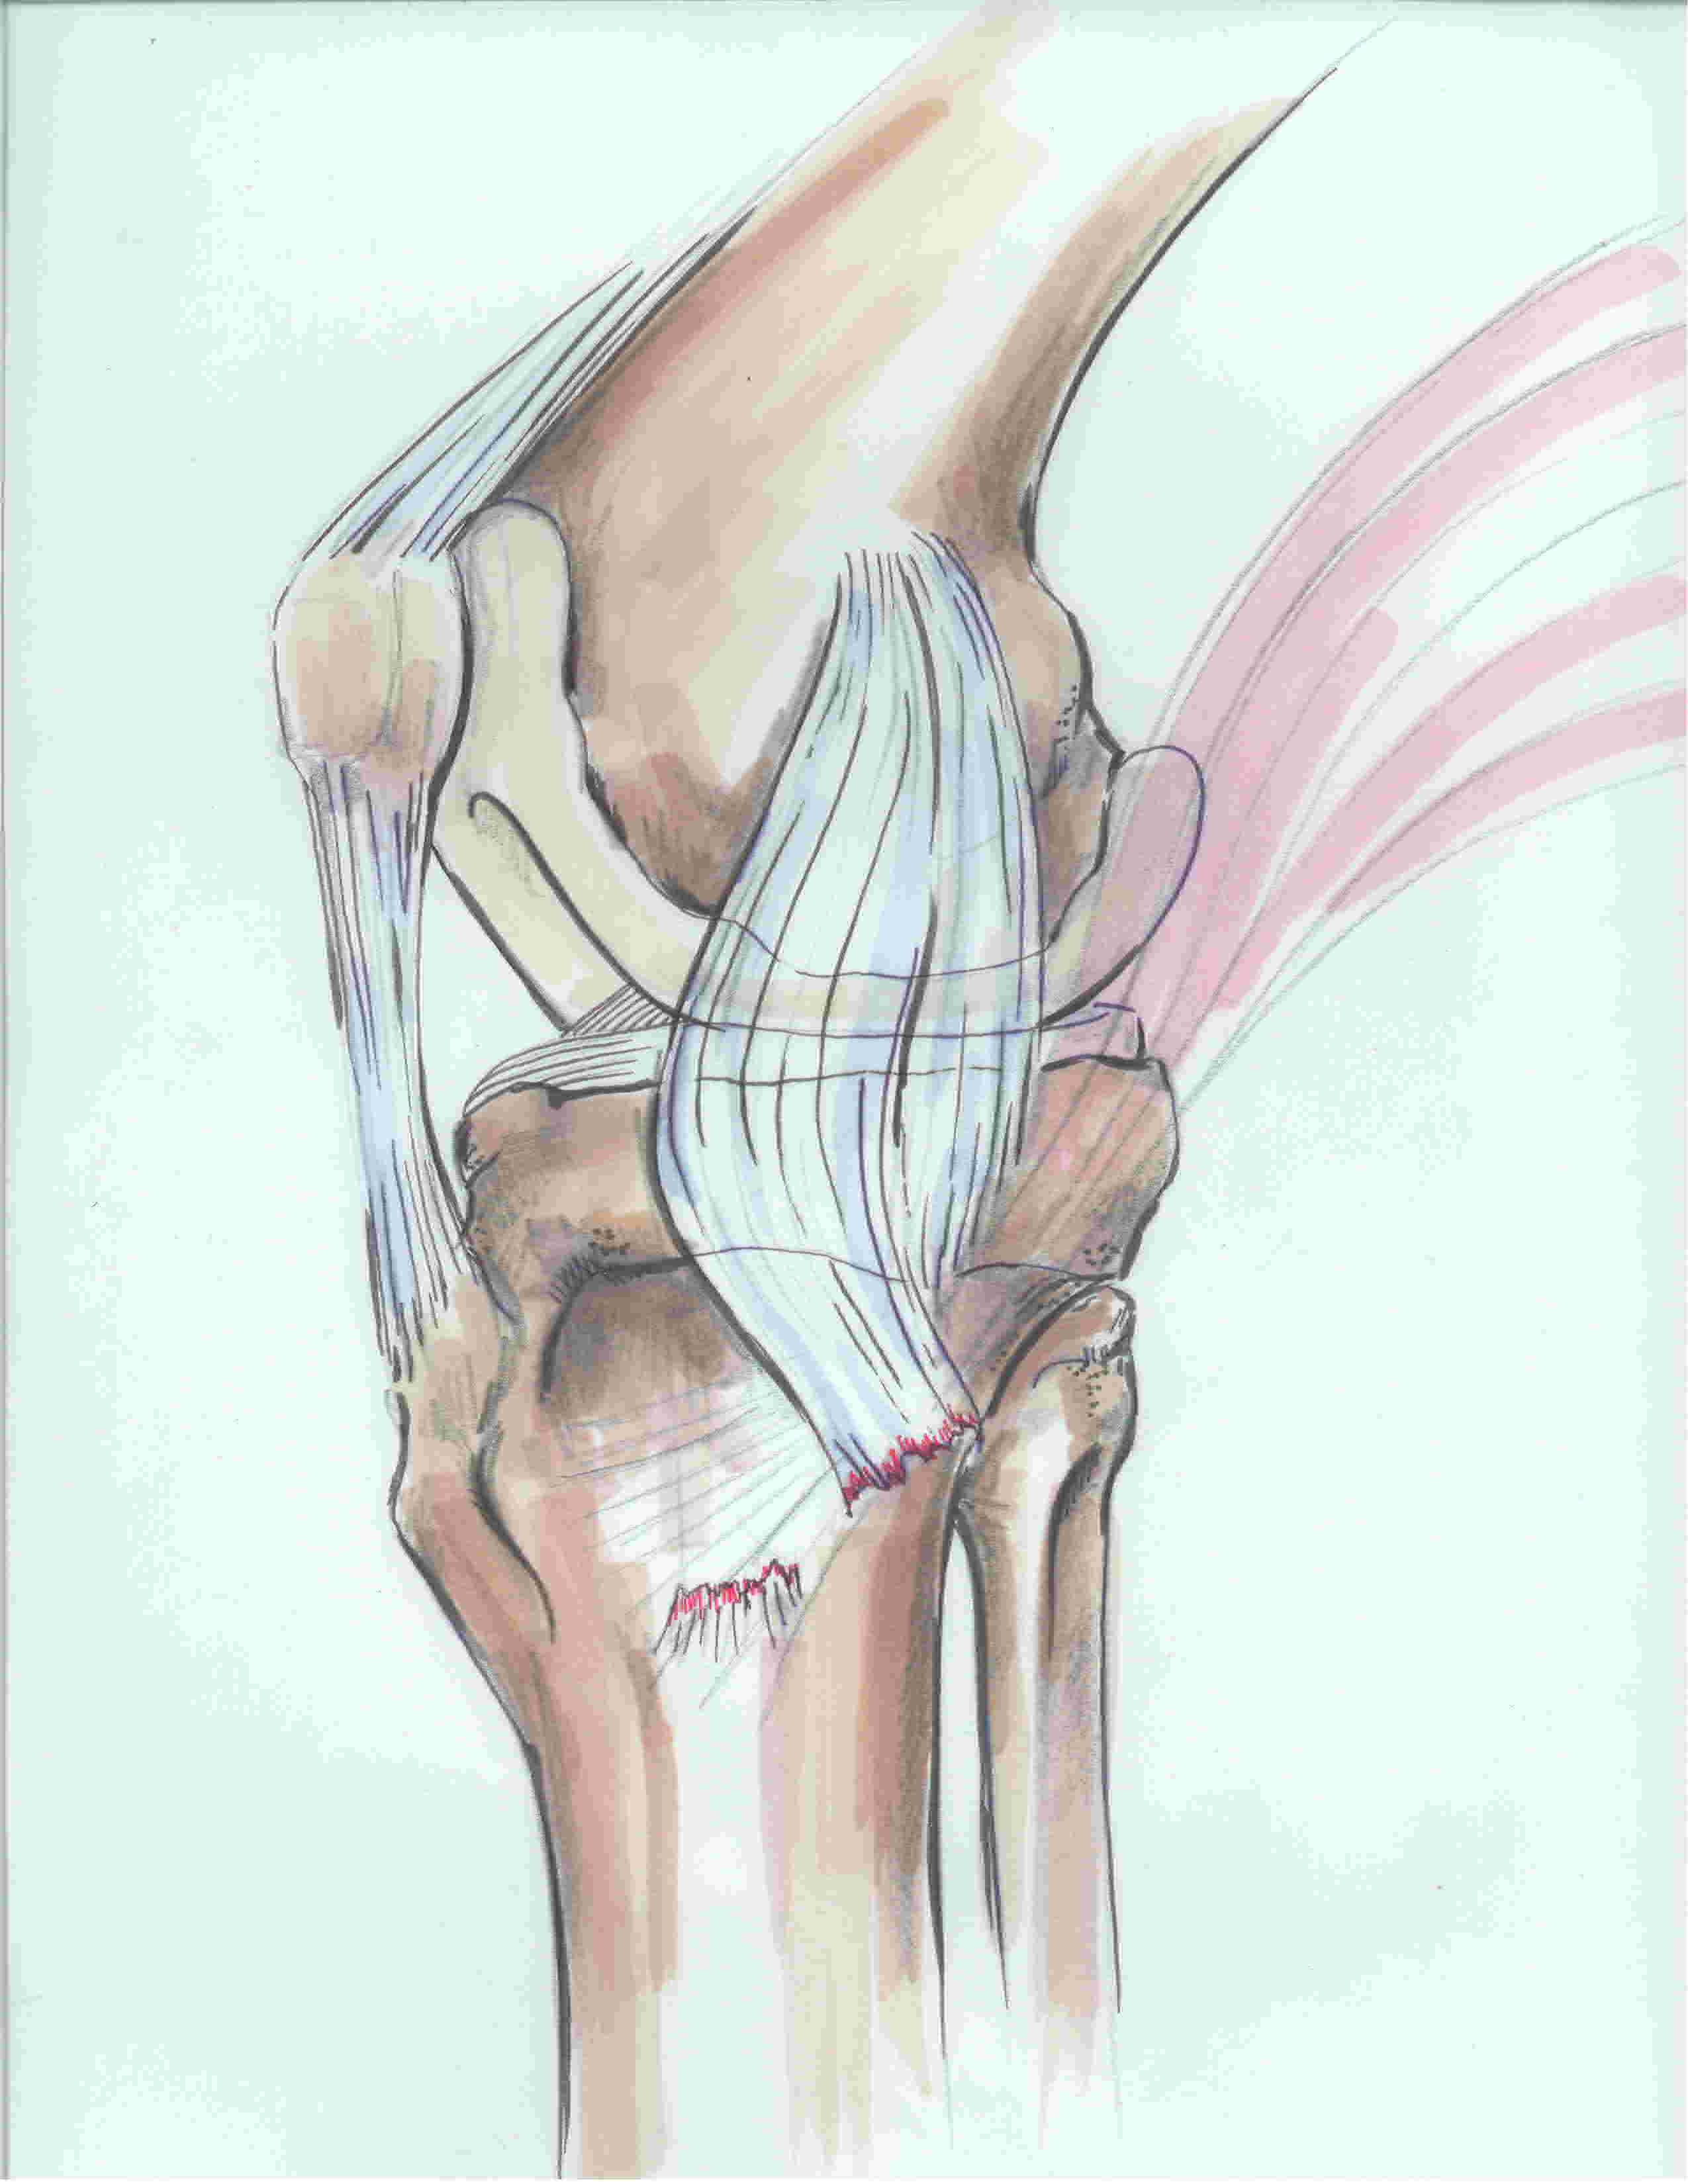

2. MCL

| Superficial MCL | Deep MCL |

|---|---|

|

Triangular in shape Origin: 3 mm proximal and 5 mm posterior to the epicondyle Insertion: 6 cm distal to the joint line onto posteromedial tibia, deep to pes anserinus Anterior margin free |

Deep to MCL Origin: inferior to medial epicondyle Insertion: 1 cm below joint line Meniscofemoral and meniscotibial ligaments - capsular thickening |

3. Posteromedial corner (5 components)

i) Posterior oblique ligament (POL)

- behind / posterior the superficial MCL

- origin: femur posterior and distal to adductor tubercle

- insertion: central arm onto posterior tibia below articular surface and the posteromedial capsule

ii) Semimembranosus

- attaches to the posteromedial corner of the tibia just below the joint line

- also has extensions blending with POL and OPL

- important dynamic stabiliser

iii) Oblique Popliteal Ligament (OPL)

- extension of semimembranosus

- extents laterally towards lateral femoral condyle

- thickens posteromedial capsule

iv) posteromedial joint capsule

v) Posterior horn of medial meniscus